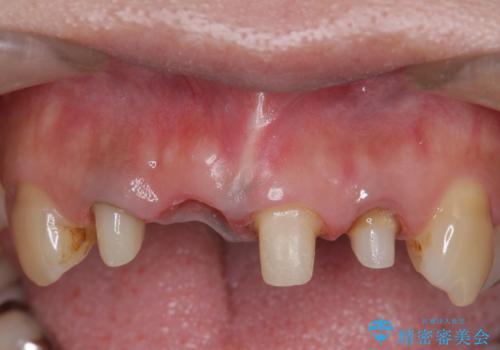

- 右上の前歯が折れてしまったので診て欲しいといらっしゃった方の症例です。

右上1番目の歯は保存不可能だったため抜歯し、ブリッジによる補綴を行いました。